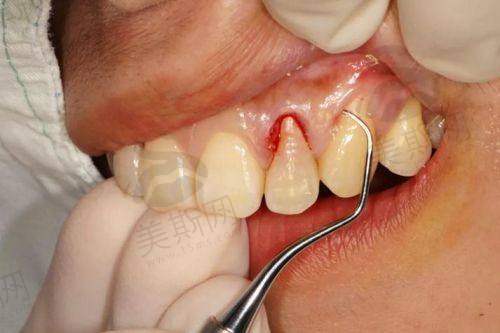

患者李女士(45岁)因慢性牙周炎导致3颗前牙松动Ⅲ度,牙龈退缩2mm,多家医院建议拔除后种植。易纯医生评估后,制定“牙周基础治疗 + 引导组织再生 + 即刻种植”方案:精良行龈下刮治控制炎症,2个月后采用GBR技术重建牙槽骨,同期植入种植体并放置美学基台。术后6个月,种植体周围软组织丰满度达理想状态,牙龈缘曲线自然,与邻牙协调一致。李女士表示:“没想到松动牙还能保住,现在笑起来更自信了,易医生的技术和细心让我完全摆脱了看牙恐惧。”